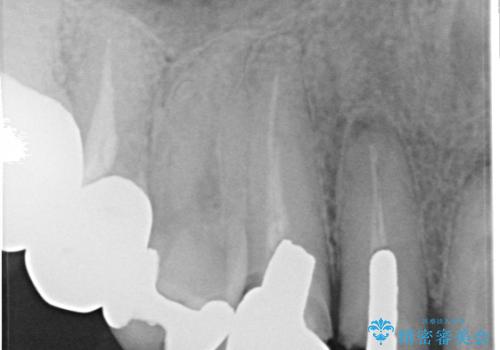

レントゲンを撮影すると、適合不良のかぶせ物が装着されており、根の治療も不十分であることが確認されました。

適合不良のかぶせ物をすべて除去して、根の中の治療から再治療を行うこととなりました。